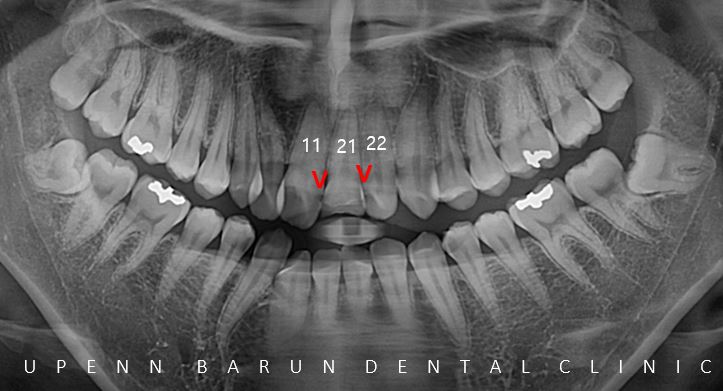

교정치료 전 엑스레이 촬영 결과

앞니 사이사이에 충치가 있을뿐만 아니라

위앞니가 부러져 있는 상태였어요 ㅠㅠ